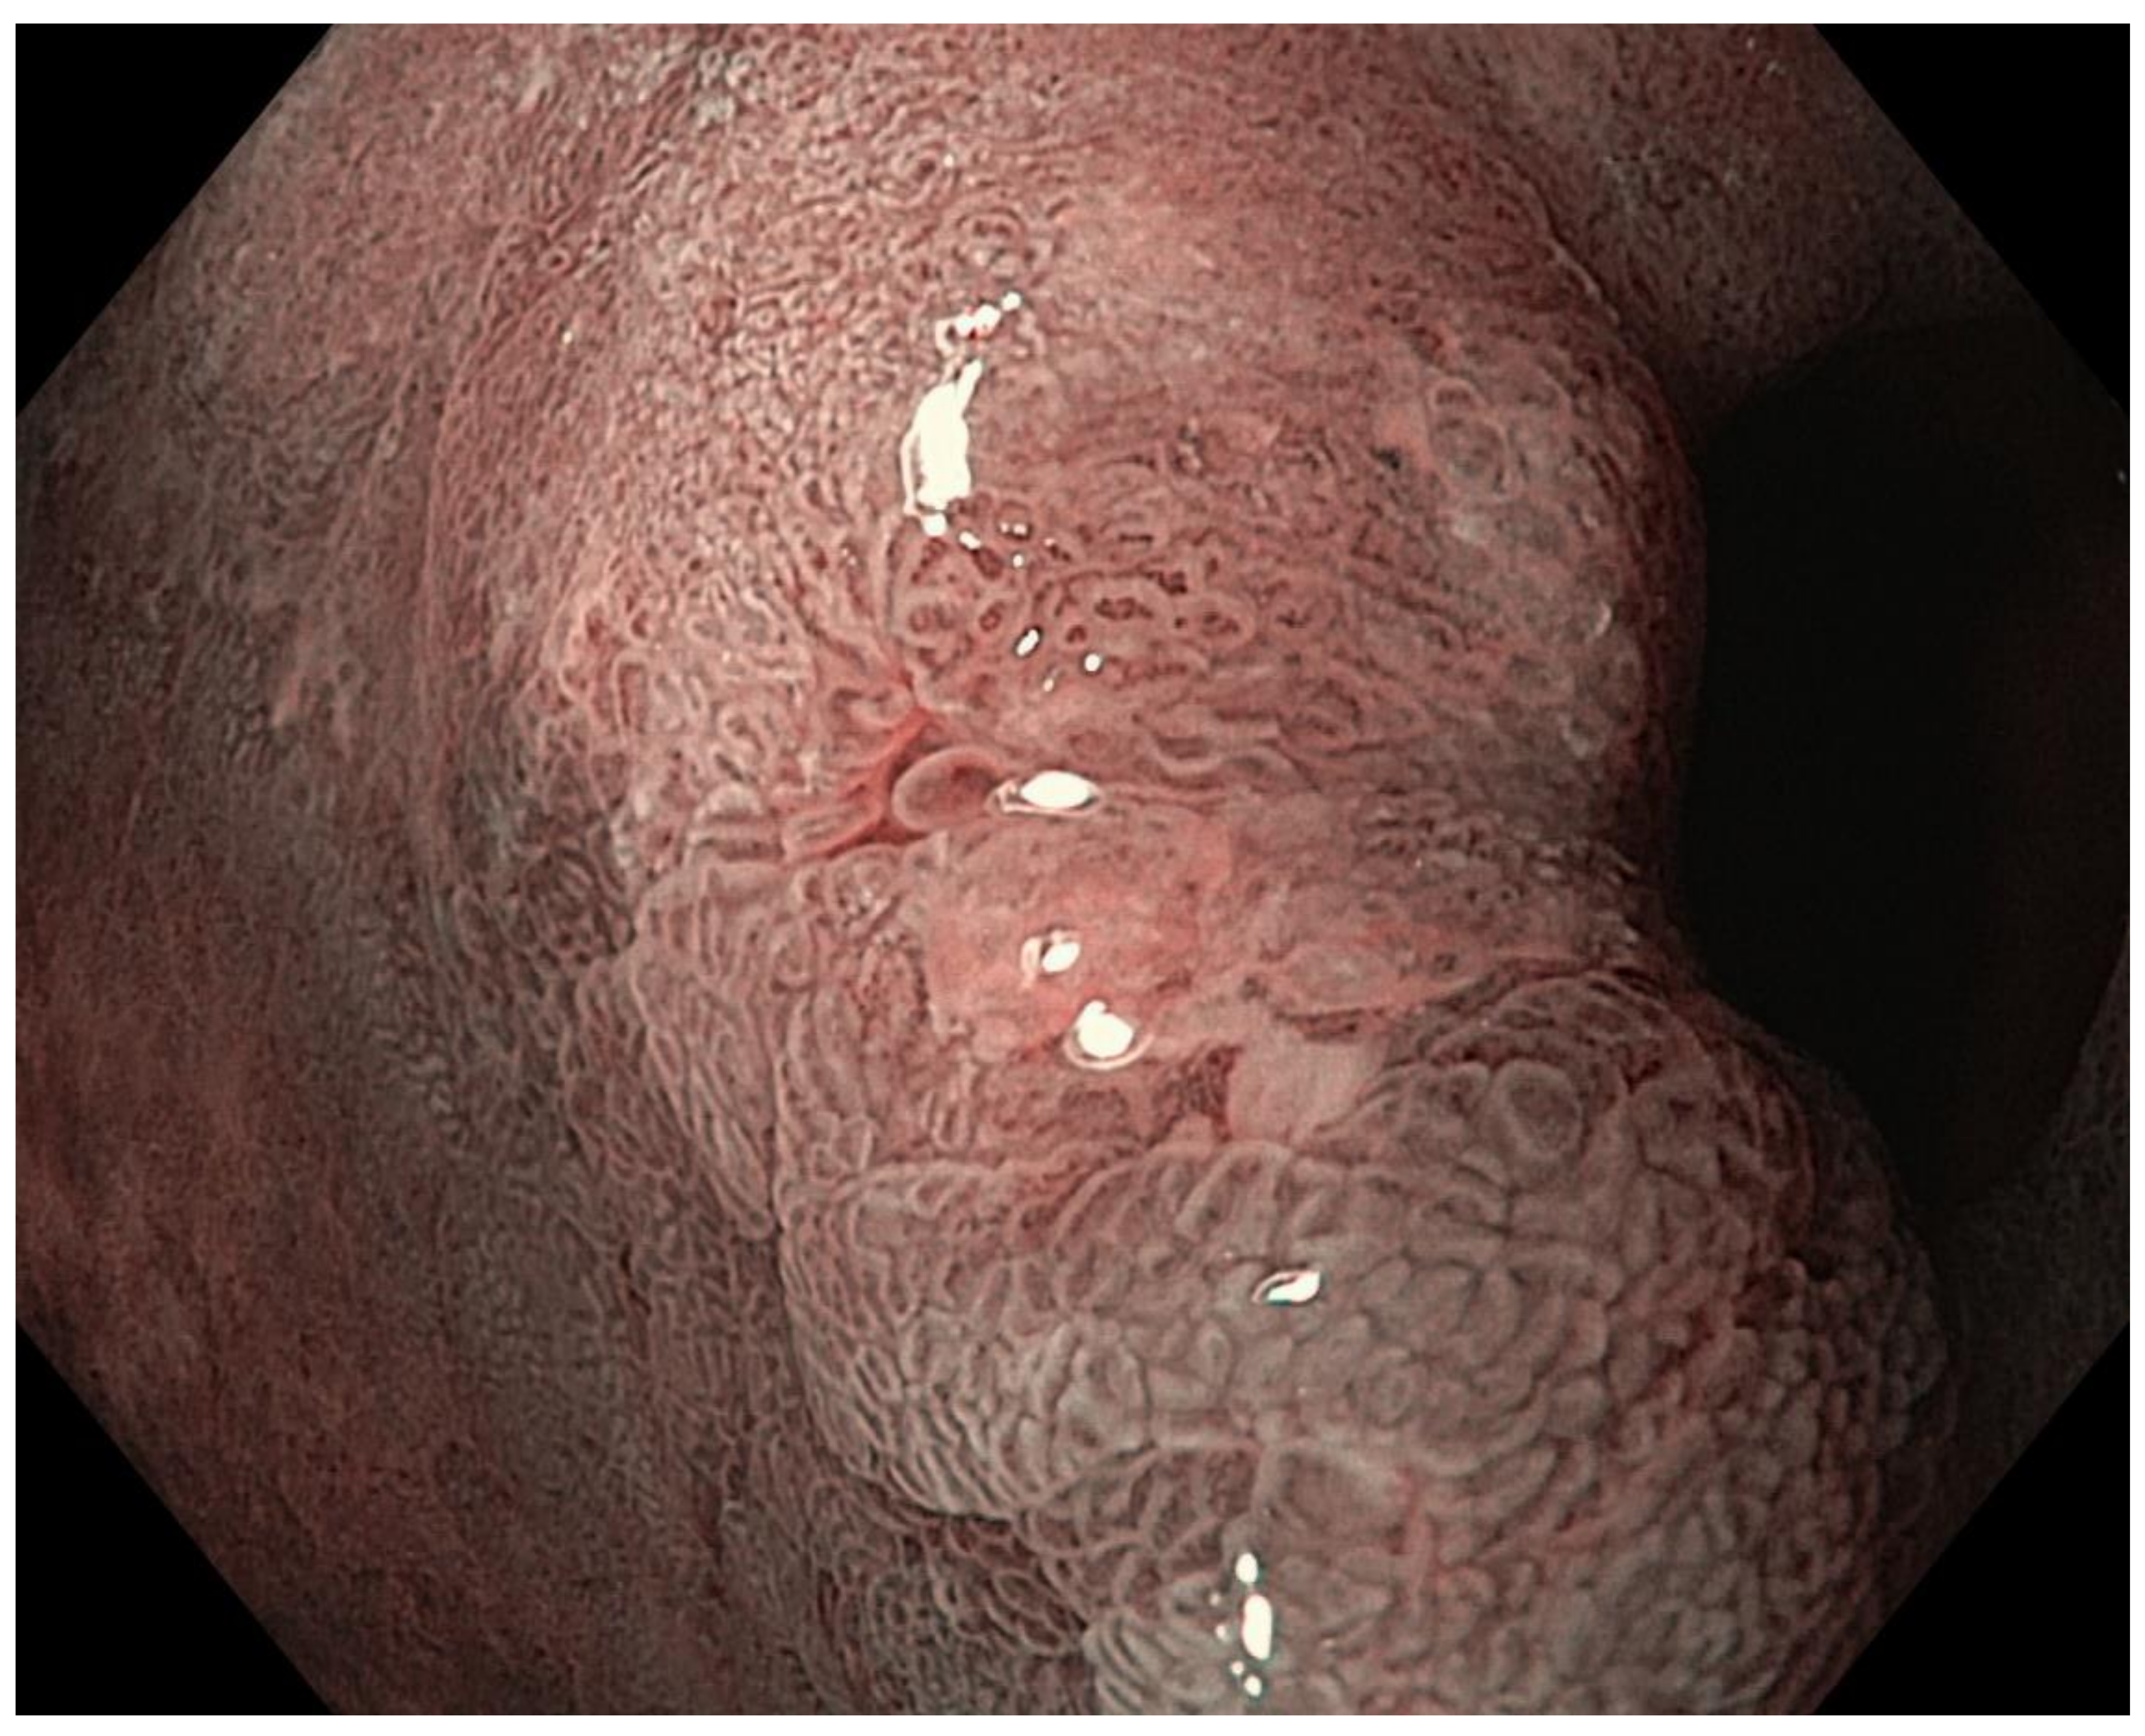

Grey-white mildly elevated plaques which are surrounded by patchy pink and pale areas are the typical appearance of intestinal metaplasia, Figure 5 and Figure 6. Standard endoscopy alone is not reliable for the diagnosis of intestinal metaplasia. Using image-enhanced and magnification endoscopy, intestinal metaplasia can be recognized in the gastric body by a “groove-type pattern”, which is similar to that observed in the antrum due to the oblique structure of the glands, and is easy to differentiate from the normal straight glands. Intestinal metaplasia in the antrum however is difficult to characterise, as the pre-existing oblique glands are not dissimilar to the “grooved” glands of intestinalisation. The “light blue crest” and “marginal turbid band” (see below) are helpful features to distinguish gastric intestinal metaplasia from the normal antral mucosa, Figure 7 [113].